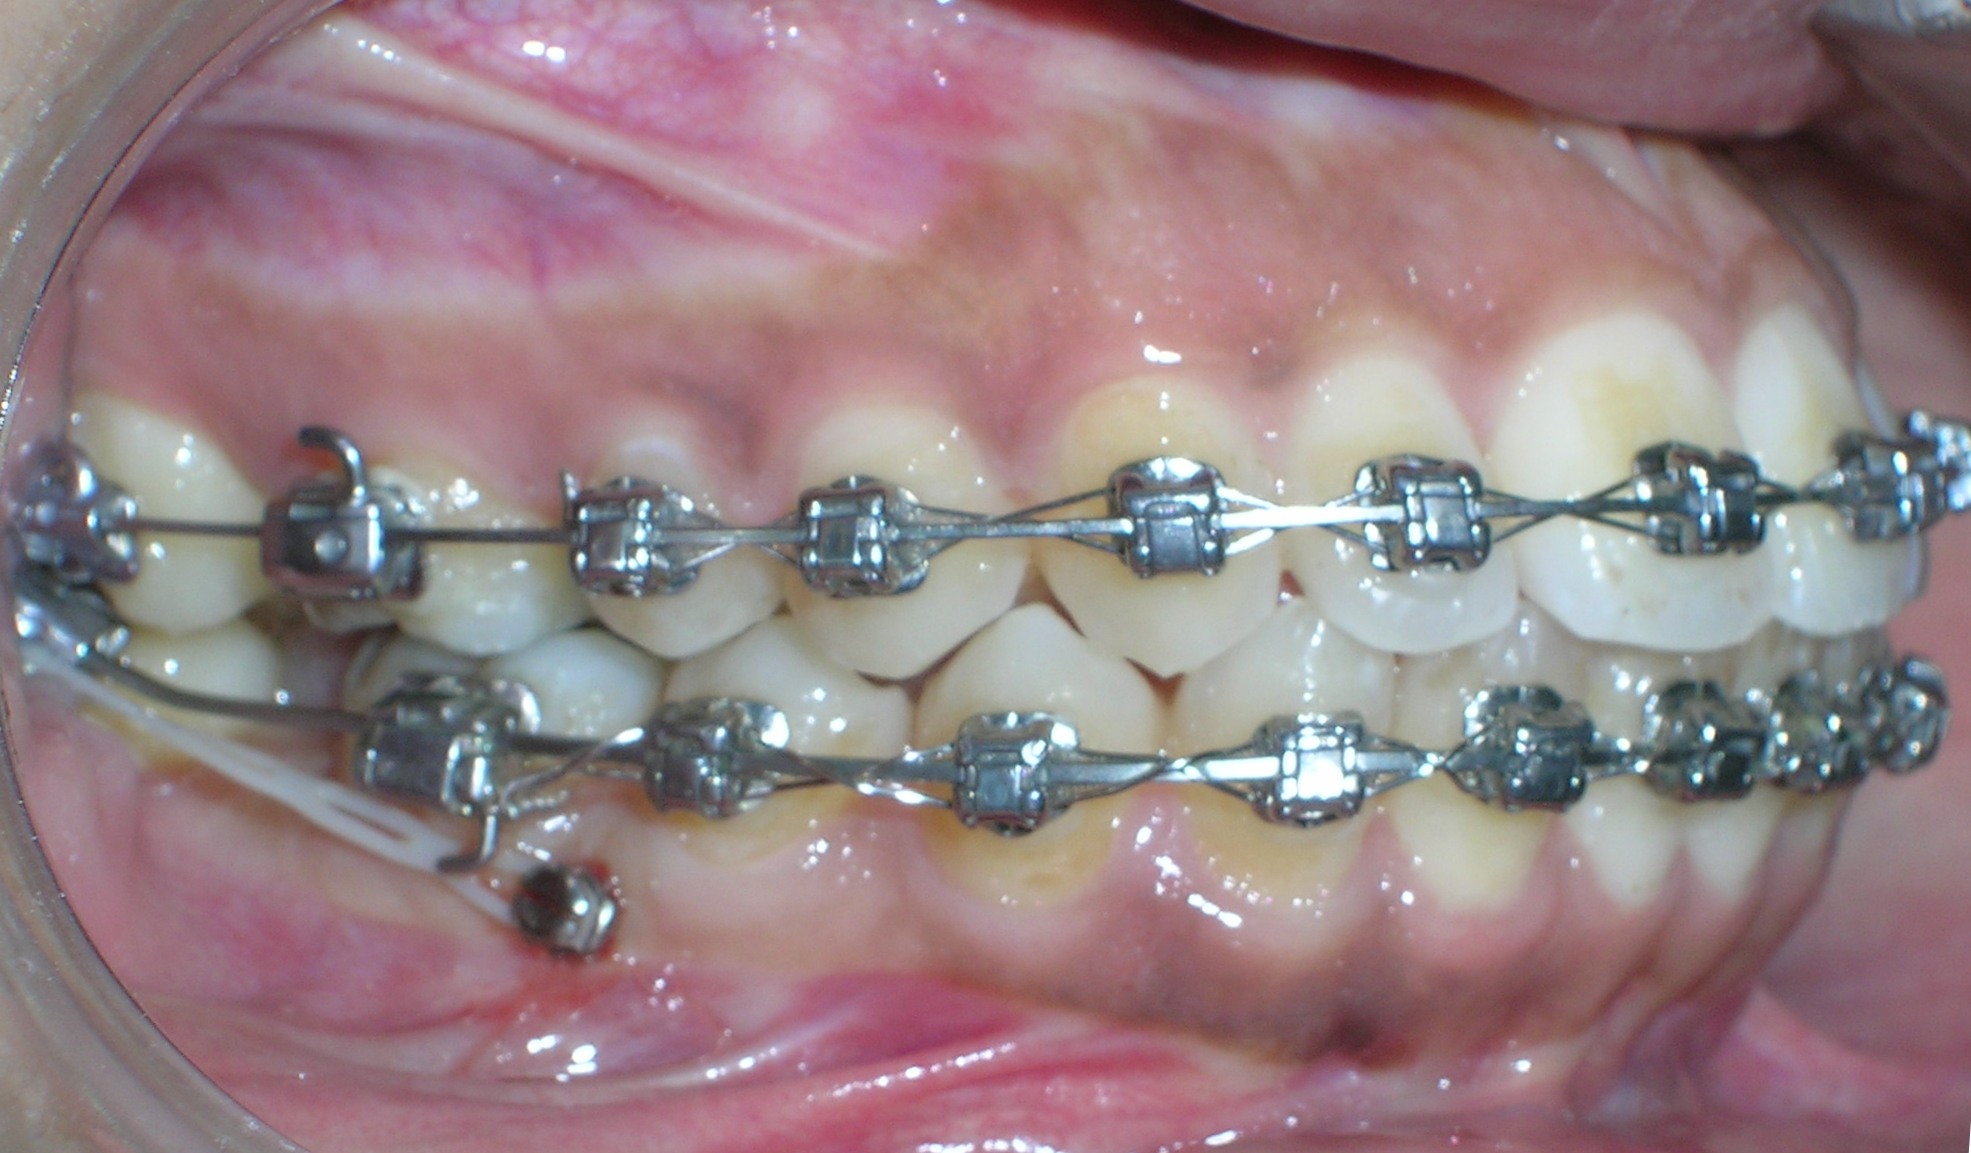

تعريف عام تقويم الأسنان هو فرع من طبِ الأسنان يَتخصّصُ في التشخيصِ ومنعِ ومعالجةِ الشذوذات والتغيرات في الأسنانِ والعظام الفكية الوجهية من حيث الموضع والحجم وعلاقة الأسنان والفكين ببعضها البعض. إنه يتعلق بتقويم الأسنان والفكين من أجل تحسين الابتسامة وصحة الفم. تعني كلمة "أورثو" أن الشيء سليم أو مستقيم في قوامه وتعني كلمة "أودونت" سنا. في العادة يوصي طبيب الأسنان بتركيب أجهزة تقويم الأسنان لتحسين المظهر الطبيعي لوجه وفم المريض. تَتطلّبُ ممارسةُ التقويم المعرفة المحترفة في وضع خطة العلاج وتطبيقِ الحاصرات السنية والتحكم بها لتحريك وجَلْب الأسنانِ والشفاهِ والفكين إلى الاصطفاف الصحيحِ والتوصّلُ إلى التوازنِ الوجهيِ. فمن خلال العلاج بتقويم الأسنان يتم معالجة المشاكل الناتجة عن الأسنان المتعوجة أو المتزاحمة وبروز الفك العلوي أو العضة المفتوحة وسوء وضعية الفك واضطرابات مفاصل الفك. بعد أخذ الأشعة والصور اللازمة يقوم طبيب التقويم بالعلاج اللازم وذلك بتثبيت أسلاك من المعدن على الأسنان أو يركب له جهاز متحرك ، ويتطلب ذلك العديد من الزيارات للطبيب على فترات متباعدة يحددها الطبيب المعالج حسب حالة كل مريض ويجب على المريض الاهتمام بتفريش أسنانه خلال فترة العلاج كي يتلافى ألإصابة بتسوس الأسنان أو ألتهاث اللثة نتيجة تراكم طبقة البلاك على أسنانه وأسلاك التقويم. التقويم يُمْكِنُ أَنْ يَرْفعَ ثقة الشخص بشكله ومظهره الشخصي عندما تصبح الأسنان والفكين والشفاه بوضعها الصحيح، لكن الابتسامةَ الجذّابةَ هي فقط إحدى فوائد التقويم الذي يؤدي أيضا لتَخفيف أَو مَنْع المشاكلِ الصحية بشكل عام، وهذا ما يعطي التقويم أهمية خاصة. فقط للحصول على ابتسامة رائعة و لكن صحّية أيضاً. الأسنان الموزعة باستقامة صحيحة في الفم تُحسّنُ إلى حد كبير الناحية الوظيفية في المضغ والبلع والكلام وتجعل التنظيف أسهل وأكثر فعالية وفائدة. الابتسامة الجميلة شيء رائع سواء عند امتلاكه أو رؤيته. الابتسامة الجذابة هي البداية فقط لكن تحسن الصحة الفموية والعامة تظل من الأهدافَ الم.همة في المعالجة التقويمة. أجهزة تقويم الأسنان الأجهزة الثابتة عبارة عن وحدات تقويمية صغيرة تثبت على كل سن، حيث يمرر بداخلها سلك معدني لتتم عملية تحريك الأسنان وهناك أنواع للحاصرات وهى: معدنية ستاليس ستيل ذات لون فظي. خزفية شفافة مشابهة للون الأسنان. ذهبية معدنية مطليه باللون الذهبي. هذه الأنواع جميعها تؤدى نفس الفعالية في العلاج والاختلاف الوحيد فيها هو لونها وشكلها الخارجي فالحاصرات المعدنية هى النوع السائد في التقويم بينما الخزفية نادرا ما تستخدم لأنها أغلى من المعدنية و.تحتاج إلى رعاية أكثر لسهولة كسرها وهى مرغوبة من النساء أكثر لأنها شفافة فلا يظهر من التقويم سوى السلك المعدني. اهمية تقويم الاسنان التنفس الصحيح استخدام الأطفال للمصاصة بالطريقة الخاطئة لمدة طويلة قد يؤدي الى ضيق الفك العلوي مما يسبب تنفس الطفل من فمه بدلاُ من انفه وهذه المشكلة سوف تصحح تلقائياً عند توسيع الفك العلوي باستخدام التقويم. الكلام بشكل جيد سوف يواجه ألإنسان صعوبة في النطق الجيد وذلك بسبب عدم انطباق الأسنان بالشكل الصحيح. وعدم القدرة على النطق الصحيح قد يؤثر على نفسية ألإنسان. الشكل الجميل إذا كانت وضعية الأسنان غير صحيحة فهذا سوف يؤثر على طريقة الكلام فستجد البعض يضع يده أمام فمه والآخر يقفل شفتيه ليخفي أسنانه وهذا بدورة سوف يجعل الكلمات غير واضحة واعوجاج وتزاحم أسنان الأطفال قد يؤثر على مستواهم الدراسي وذلك لخجلهم من أسنانهم فتراهم لا يشاركون ولا يتجاوبون مع مدرسيهم مما يجعل المدرسين يأخذون فكرة وصورة غير جيدة عنهم كعدم الاهتمام. الحالات التي تحتاج الى علاج التقويم التزاحم الشديد بين الأسنان الأمامية أو الخلفية – وجود فراغات كبيرة بين الأسنان الأمامية – وجود عضة أمامية مفتوحة – وجود عضة أمامية عميقة بحيث تغطي الأسنان الأمامية العلوية الأسنان الأمامية السفلية تغطية كاملة أو قريبة من الكاملة – وجود عضة أمامية معكوسة – عدم أو سؤ تطابق الأسنان الخلفية – بروز الأسنان الأمامية |